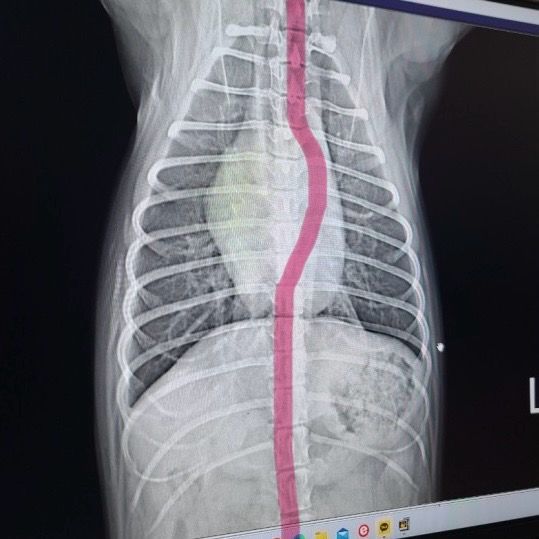

- 반려동물 건강반려동물Q. (이은수 수의사님) 하나만 더 여쭤보고싶습니다ㅠ 강아지 엑스레이 관련안녕하세요 강아지 건강검진 받고 엑스레이상 흉골이 휘었다고 했었는데요, 외부충격은 없고, 1년 전 다른 병원에서 찍은 엑스레이는 흉골 휘지 않았습니다. 사진상으로 휘어보이는거라고 하셨는데 잘못찍혔다는 말씀이실까요? 건강검진 병원에서는 1년전 다른 병원에서 찍은 엑스레이는 흉골이 휘지 않아서 폐쪽 문제일수도 있으니 ct가능한 병원가서 정확하게 보는게 좋을거같다는데, 폐에 문제가 생기면 심장이 쏠리면서 흉골이 휠수도있나요..? 엑스레이는 흉골이 휜거같아 이상해서 세번정도 찍었다고 하네요. 사진 보면 노란색 표시 흉골이 휘어있고 심장도 쏠려있습니다…잘못찍었다고 흉골이 휘고 심장도 쏠릴 수 있나요?!?첫번째 사진이 1년전 다른병원에서 찍은 엑스레이고 2,3번째가 이번에 찍은 흉골 휜 엑스레이입니다.. 3,4번째 흉골 휜 엑스레이 같은 사진인데 휜 흉골부분 노란색으로 표시해뒀습니다. R, L사진 둘 다 다른방향에서 찍은거같은데, 둘 다 휘어있습니다. 폐쪽의 문제일수도 있을까요? 기침이나 식욕감퇴 등의 다른 증상은 없고 변 상태도 좋습니다.

- 반려동물 건강반려동물Q. 강아지 엑스레이 잘못찍으면 흉골 휘어보이게 나오는건가요안녕하세요 강아지 건강검진 받고 엑스레이상 흉골이 휘었다고 했었는데요, 외부충격은 없고, 1년 전 다른 병원에서 찍은 엑스레이는 흉골 휘지 않았습니다. 사진상으로 휘어보이는거라고 하셨는데 잘못찍혔다는 말씀이실까요? 건강검진 병원에서는 1년전 다른 병원에서 찍은 엑스레이는 흉골이 휘지 않아서 폐쪽 문제일수도 있으니 ct가능한 병원가서 정확하게 보는게 좋을거같다는데, 폐에 문제가 생기면 심장이 쏠리면서 흉골이 휠수도있나요..? 엑스레이는 흉골이 휜거같아 이상해서 세번정도 찍었다고 하네요. 사진 보면 노란색 표시 흉골이 휘어있고 심장도 쏠려있습니다…잘못찍었다고 흉골이 휘고 심장도 쏠릴 수 있나요?!?첫번째 사진이 1년전 다른병원에서 찍은 엑스레이고 2,3번째가 이번에 찍은 흉골 휜 엑스레이입니다.. 3,4번째 흉골 휜 엑스레이 같은 사진인데 휜 흉골부분 노란색으로 표시해뒀습니다. R, L사진 둘 다 다른방향에서 찍은거같은데, 둘 다 휘어있습니다. 폐쪽의 문제일수도 있을까요? 기침이나 식욕감퇴 등의 다른 증상은 없고 변 상태도 좋습니다.

- 반려동물 건강반려동물Q. 강아지 엑스레이 흉골이 휘었다는데오안녕하세요 강아지 건강검진 받고 엑스레이상 흉골이 휘었다고 했었는데요, 외부충격은 없고, 1년 전 다른 병원에서 찍은 엑스레이는 흉골 휘지 않았습니다. 사진상으로 휘어보이는거라고 하셨는데 잘못찍혔다는 말씀이실까요? 건강검진 병원에서는 1년전 다른 병원에서 찍은 엑스레이는 흉골이 휘지 않아서 폐쪽 문제일수도 있으니 ct가능한 병원가서 정확하게 보는게 좋을거같다는데, 폐에 문제가 생기면 심장이 쏠리면서 흉골이 휠수도있나요..? 엑스레이는 흉골이 휜거같아 이상해서 세번정도 찍었다고 하네요. 사진 보면 노란색 표시 흉골이 휘어있고 심장도 쏠려있습니다…잘못찍었다고 흉골이 휘고 심장도 쏠릴 수 있나요?!? 첫번째 사진이 1년전 다른병원에서 찍은 엑스레이고 2,3번째가 이번에 찍은 흉골 휜 엑스레이입니다.. 3,4번째 흉골 휜 엑스레이 같은 사진인데 휜 흉골부분 노란색으로 표시해뒀습니다. R, L사진 둘 다 다른방향에서 찍은거같은데, 둘 다 휘어있습니다. 폐쪽의 문제일수도 있을까요? 기침이나 식욕감퇴 등의 다른 증상은 없고 변 상태도 좋습니다.

- 반려동물 건강반려동물Q. 강아지 엑스레이 흉골 휘었다는데요.이은수 수의사님. 강아지 흉골 관련해서 답주셨는데 이 사진처럼 흉골이 휘게나왔는데 이게 촬영상이 돌아가면서 휘어보인다는 말씀이실까요? 촬영상이 돌아가면서 휘어보인다는 내용이 이해가 안가서요. 옆부분 엑스레이상 오목가슴은 아닙니다.ㅠㅠ

- 반려동물 건강반려동물Q. 강아지 엑스레이 흉골 휘었다는데요 ..안녕하세요 강아지 건강검진을했는데 흉골이 휘었다고해서요. 첫번째사진은 1년전이고 2,3번째 사진은 이번년도 사진입니다. 혹시 이런경우 원인은 무엇인가요? 외부충격은 없었습니다..

- 반려동물 건강반려동물Q. 강아지 엑스레이 흉골이 휘어보이는 이유안녕하세요, 강아지 건강검진을 받았는데 엑스레이상 흉골이 휘어보인다해서요, 외부충격은 없었고 기침이나 등 다른 증상은 없습니다. 일년전 다른 병원에서 건강검진 때 엑스레이에선 휘어보이지않는데 엑스레이를 잘못찍으면 흉골이 휘어보일수있나요? 아니면 다른쪽에 문제가 있을 수 있는건가요.. 첨부한 사진은 실제 사진이 아니고 빨갛게 그린게 저희 강아지 엑스레이상 휘게 나온걸 보여드리고 싶어서 첨부했습니다. 정면 엑스레이에서 흉골이 사진 빨간 부분처럼 좀 휘게 나왔습니다.

- 반려동물 건강반려동물Q. 강아지 엑스레에 찍을 때 자세 이상하면 흉골이 휘어보이게 나올수도 있나요? 강아지 엑스레에 찍을 때 자세 이상하면 흉골이 휘어보이게 나올수도 있나요? 건강검진 했는데 흉골이 휘었대서요.. 작년 다른 병원에서 검진했을 때는 괜찮았는데 외부충격도 없었는데 1년만에 휘을수가있나요.?.. 외부 충격 아니면 폐쪽 문제일수도있다는데 외부충격은 없었고, 기침이나 다른 증상도 없어서요. 혹시 엑스레이 찍을 때 자세가 잘못되면 흉골이 휘게 나오기도 하나요